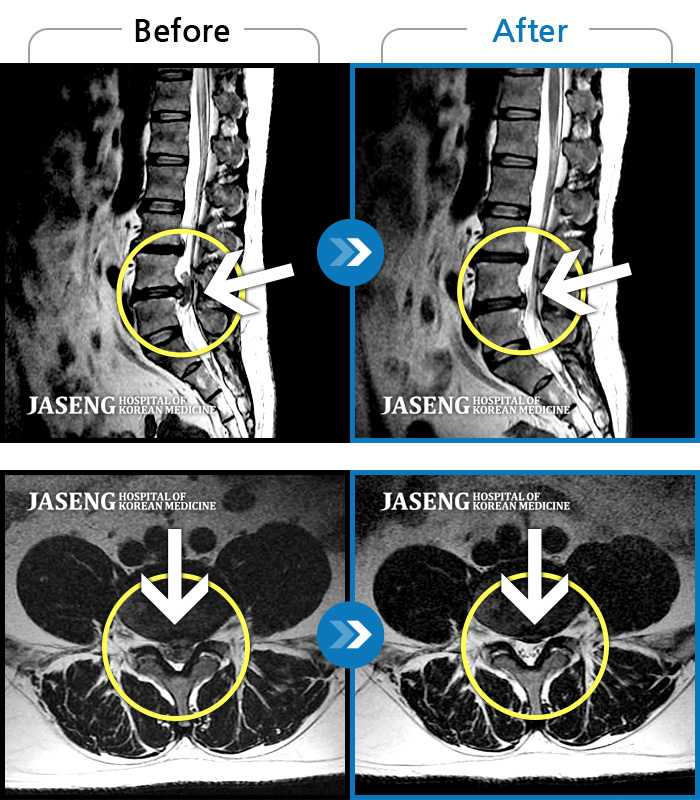

[뱸] 19.11.28~25.05.06